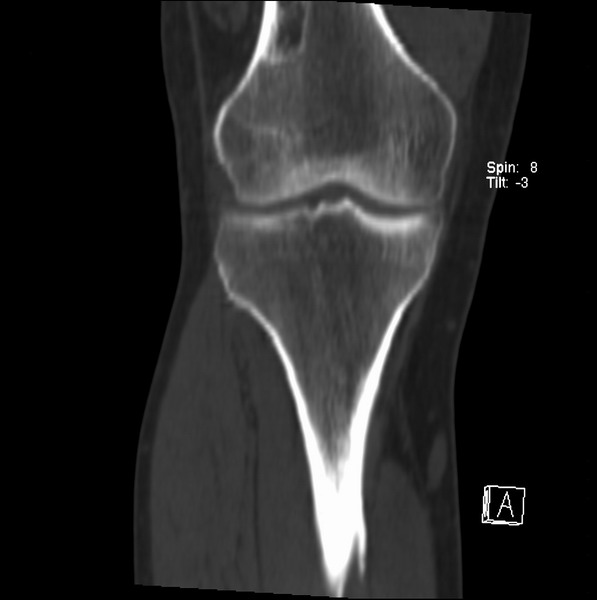

标题: CT21959:骨肿瘤请会诊。

右侧膝关节疼痛一月

男、48

股骨下段、胫骨上段。

1、股骨干骺端病变考虑干骺端纤维性皮质缺损愈后(非骨化性纤维瘤)改变,胫骨近端内生骨瘤(或干骺端纤维性皮质缺损愈后改变);

2、骨关节炎,骨质增生,股骨外侧髁退变性囊肿(关节面软骨下囊肿);

股骨干骺端病变考虑干骺端纤维性皮质缺损愈后(非骨化性纤维瘤)改变,胫骨近端内生骨瘤(或干骺端纤维性皮质缺损愈后改变);

1、股骨干骺端病变考虑干骺端纤维性皮质缺损愈后(非骨化性纤维瘤)改变,胫骨近端内生骨瘤;

股骨干骺端病变考虑非骨化性纤维瘤。

支持非骨化性纤维瘤

非骨化性纤维瘤